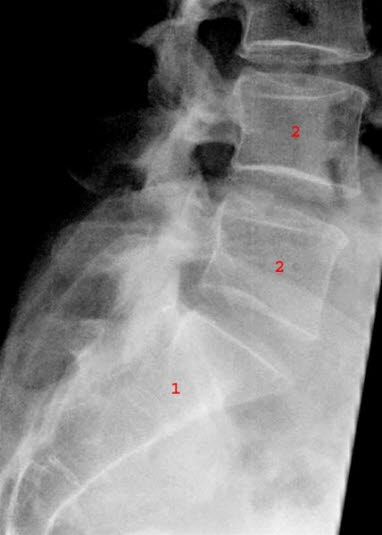

Røntgen utelukker andre brudd i bekkenet og kan vise om halebeinet er ute av stilling eller ikke. Et eventuelt brudd i halebeinet er ofte vanskelig å påvise ved røntgen.